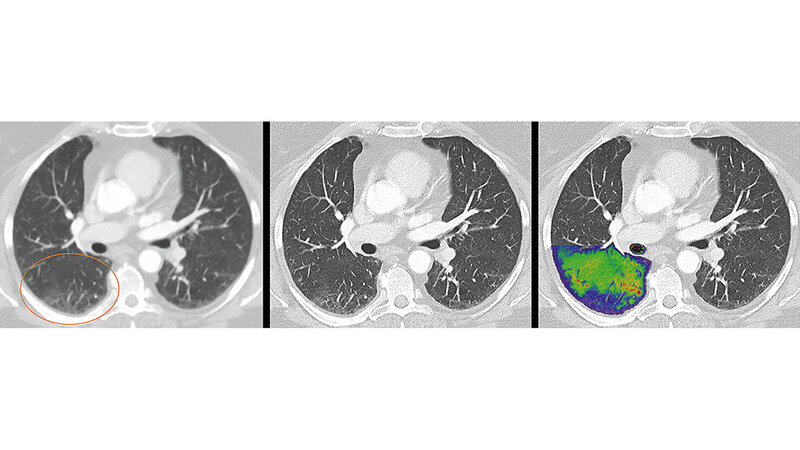

Mit einem völlig neuartigen Systemkonzept und einer bahnbrechend neuen Detektortechnologie bereiten die CT-Experten den Weg für eine neue Ära der Computertomografie, die die Grundlage vieler medizinischen Entscheidungen bildet, betont das Unternehmen. Mithilfe der revolutionären Bilder quantenzählender CTs sollen mehr Menschen in aller Welt von präziseren und schonenderen Untersuchungen bei niedriger Strahlen- und Kontrastmitteldosis profitieren können – in der Onkologie und bei der Herz-Diagnostik ebenso wie etwa bei der Verlaufskontrolle bei COVID-19 oder anderen Lungenerkrankungen. Der quantenzählende Computertomograf vereine bislang unerreicht hohe Bildschärfe und -kontraste mit extrem kurzer Aufnahmezeit und liefere neue diagnostische Informationen, die auf herkömmlichen CT-Bildern nicht zu sehen seien. Der Deutsche Zukunftspreis ist eine der höchsten deutschen Auszeichnungen für Technik und Innovation und wird am 17. November 2021 von Bundespräsident Frank-Walter Steinmeier in Berlin verliehen. Das Produkt befindet sich in der Entwicklungsphase und ist deshalb noch nicht käuflich zu erwerben. Die zukünftige Verfügbarkeit kann laut Siemens Healthineers nicht garantiert werden.